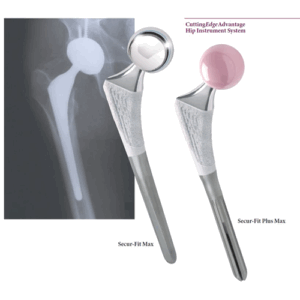

Бедренные стержни Secur-Fit Advanced

Флагманская разработка Stryker в области бедренных компонентов тазобедренных эндопротезов. При разработке учтен более чем 20-летний опыт применения других моделей. Особенности конструкции позволяют обеспечить большую степень свободы движений: сгибание/разгибание — до 215°, отведение в сторону — до 76°, вращение в суставе — до 182°. Проксимальный конец стержней сконструирован таким образом, что оптимально распределяет все виды нагрузок, воздействующих на тазобедренный сустав как в покое, так и при движении.

Бедренный стержень изготовлен из титана, на который в области наиболее плотно соприкасающейся с костной тканью имеется покрытие Stryker PureFix HA, обеспечивающее более надежное сцепление импланта с костью. Улучшенная геометрия шейки, имеющей овоидное сечение обеспечивает повышенную свободу движений в суставе при сохранении стабильности стержня.

Бедренный стержень Secur-Fit Plus Max позволяет успешно проводить эндопротезирование у пациентов с любыми аномалиями размеров бедренной кости и ее канала с помощью одной системы немодульных имплантатов.